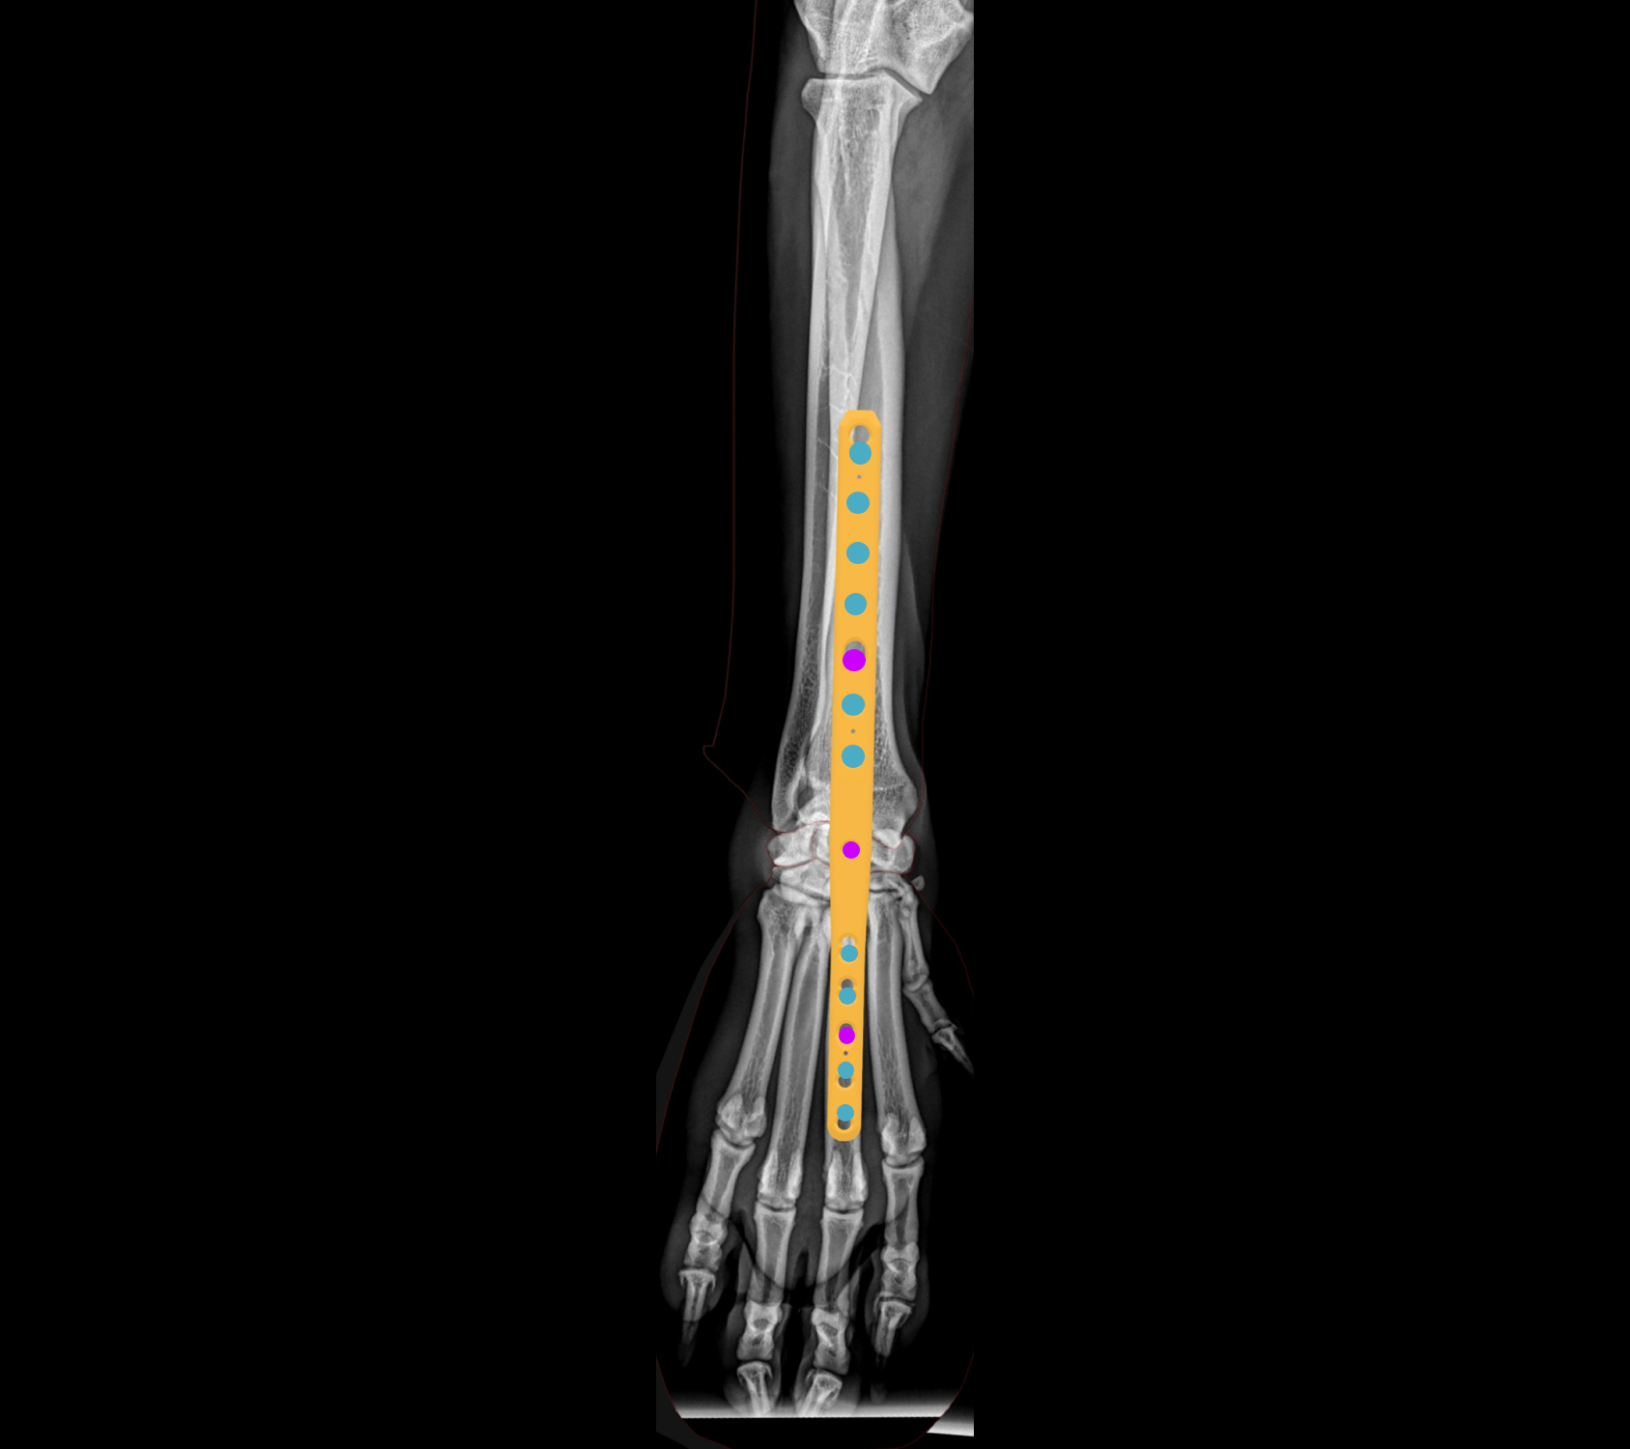

En ocasiones nos enfrentamos al manejo de patologías o condiciones ortopédicas muy complejas, que no pueden ser manejadas con implantes quirúrgicos estándar. Por ello contamos con la posibilidad de diseñar implantes customizados para los casos especiales.

La customización de implantes quirúrgicos se refiere a la adaptación de los mismos a las necesidades de cada paciente, siendo personalizados a la anatomía única de cada individuo.

Esto se consigue gracias a los avances en la tecnología de fabricación, como la impresión 3D. Con esta tecnología se pueden crear implantes personalizados tanto en acero quirúrgico como en titanio a partir de imágenes médicas de tomografías computerizadas (TC) o resonancias magnéticas (RM).